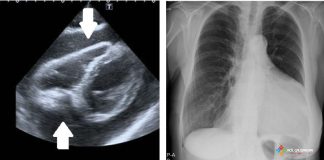

Atrial Fibrilasyon Kılavuzu ESC 2024

Avrupa Kardiyoloji Derneği (ESC) ve Avrupa Kardiyo-Torasik Cerrahi Derneği (EACTS) tarafından 2024 yılında Atrial Fibrilasyon Kılavuzu güncellendi. Bu Kılavuz 2020 yılında ve daha önce...